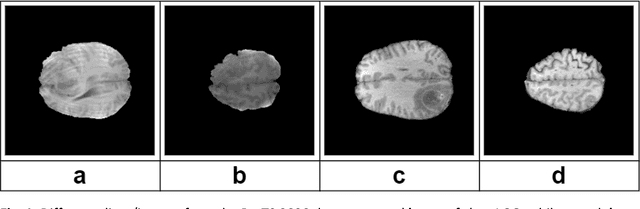

Abstract:The deep learning-based analysis of medical images suffers from data scarcity because of high annotation costs and privacy concerns. Researchers in this domain have used transfer learning to avoid overfitting when using complex architectures. However, the domain differences between pre-training and downstream data hamper the performance of the downstream task. Some recent studies have successfully used domain-adaptive pre-training (DAPT) to address this issue. In DAPT, models are initialized with the generic dataset pre-trained weights, and further pre-training is performed using a moderately sized in-domain dataset (medical images). Although this technique achieved good results for the downstream tasks in terms of accuracy and robustness, it is computationally expensive even when the datasets for DAPT are moderately sized. These compute-intensive techniques and models impact the environment negatively and create an uneven playing field for researchers with limited resources. This study proposed computationally efficient DAPT without compromising the downstream accuracy and robustness. This study proposes three techniques for this purpose, where the first (partial DAPT) performs DAPT on a subset of layers. The second one adopts a hybrid strategy (hybrid DAPT) by performing partial DAPT for a few epochs and then full DAPT for the remaining epochs. The third technique performs DAPT on simplified variants of the base architecture. The results showed that compared to the standard DAPT (full DAPT), the hybrid DAPT technique achieved better performance on the development and external datasets. In contrast, simplified architectures (after DAPT) achieved the best robustness while achieving modest performance on the development dataset .